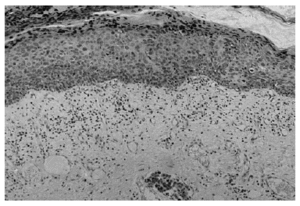

Se realizó una biopsia amplia de la lesión, incluyendo la tumoración nodular. En el examen histopatológico se podía observar una epidermis eosinófila, con una desestructuración que afectaba todo su espesor, ocupada en todo su grosor por queratinocitos atípi-cos con frecuentes mitosis, la mayoría de ellas atípicas. En el estrato córneo había hiperqueratosis, con áreas de paraqueratosis. En dermis superficial existía un infiltrado inflamatorio crónico en banda formado predominantemente por linfocitos con algún histiocito aislado (fig. 2).

Fig. 2.--Alteración de todo el espesor de la epidermis circundante, con paraqueratosis, células disqueratósicas y mitosis.